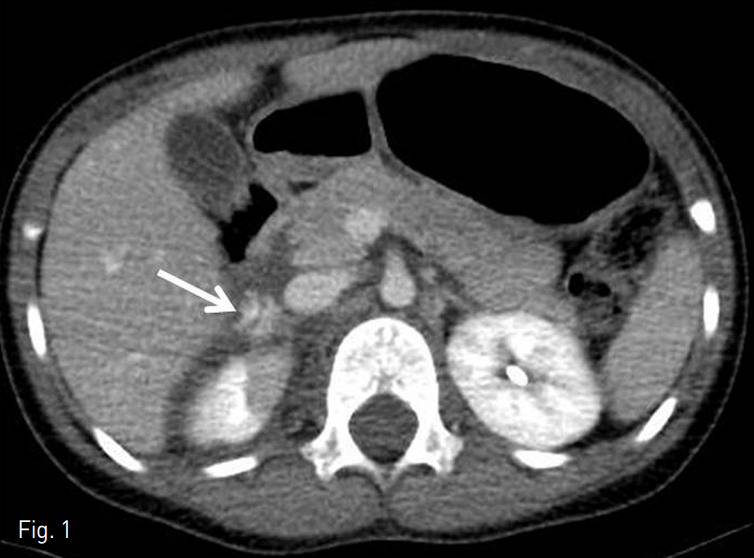

조영제를 사용한 복부 전산화단층촬영 상 오른쪽 간엽에 간열상이 확인되었고, 오른쪽 부신의 열상과 활동성 출혈 및 후복막 혈종이 확인되었다 (Fig.1).

Fig. 1

Contrast-enhanced CT demonstrates active bleeding at the right adrenal gland with ipsilateral hematoma in retroperitoneum.